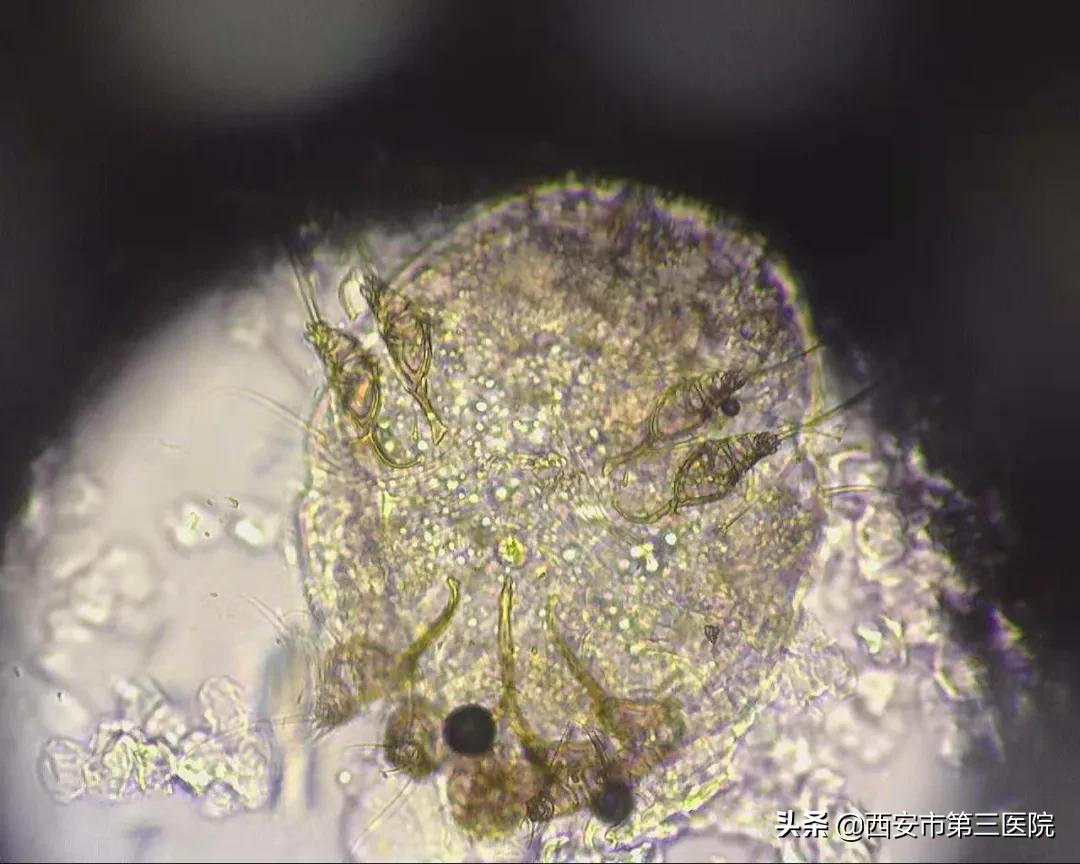

皮肤健康|易被忽视的集体宿舍杀手--疥疮